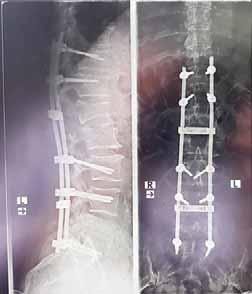

Zaopatrzenie chirurgiczne uszkodzenia -